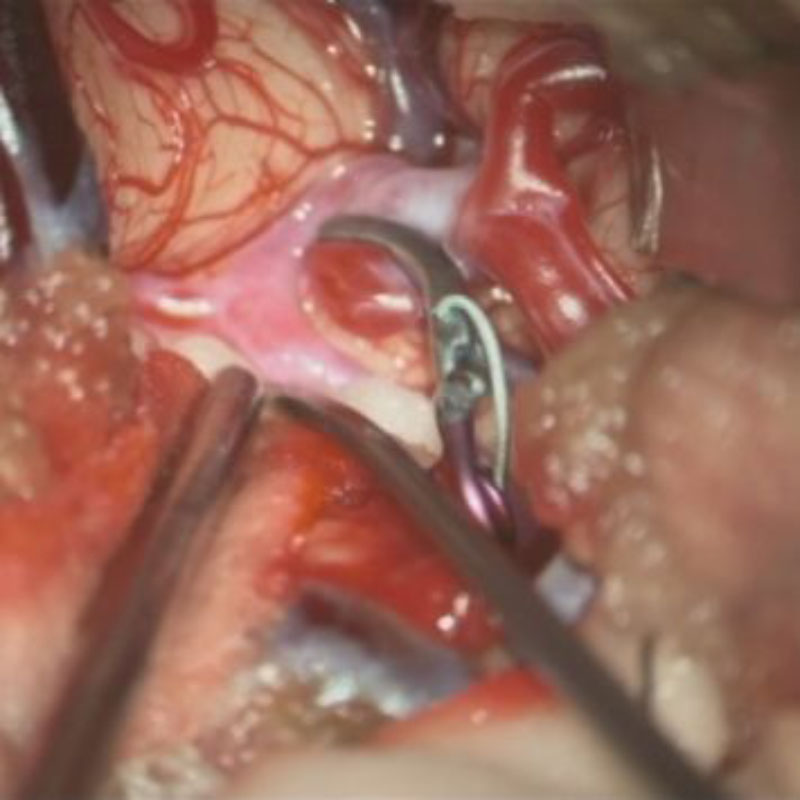

手術前

クリップ前

クリップ後

手術後